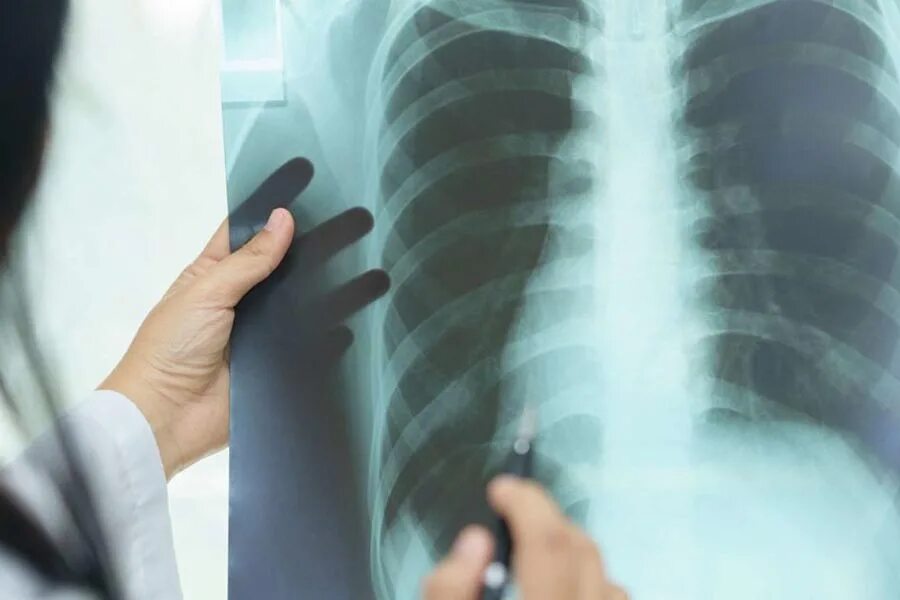

Почему в легких